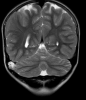

Episodios intermitentes de parestesias ascendentes en MSI y en ocasiones afasia asociada, de 6 años evolución, diagnosticados de crisis parciales y tratados con Levetiracetam. Exploración física sin evidencia de deterioro cognitivo ni otras alteraciones. En...

Neurología: Epilepsia | Patología cerebrovascular | Trastornos cognitivosEtiología: DegenerativoDiagnóstico final: Angiopatía amioide. Siderosis cortical superficial del sistema nervioso central.Nivel de certeza: